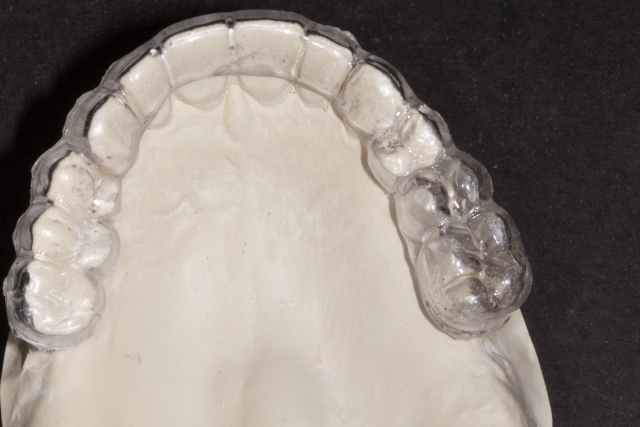

3. Using 1.5 mm clear splint material, do a vacuform over the denture teeth or model of the wax-up.

4. The appliance should then be trimmed so that the desired gingival levels of the final restorations are intact. The remaining teeth should be trimmed back so that 1-2 mm of overlapping acrylic remains to stabilize the template. This is an important landmark for the surgeon.

5. Using a radiopaque self-curing methylmethacrylate mixed to a putty consistency, fill the space left by the denture teeth or wax-up.

6. Trim the excess acylic back to the gingival margins.

7. Spot the desired exit point of the implant platform on occlusal surface of the teeth.

8. Using a 2 mm twist drill or disposable implant drill cut a hole through the acrylic until the drill touches the stone model.

9. Clean up the edges using an acrylic finishing bur.

10. When tried in, the template should be solid and stable and have a “snap-fit.”